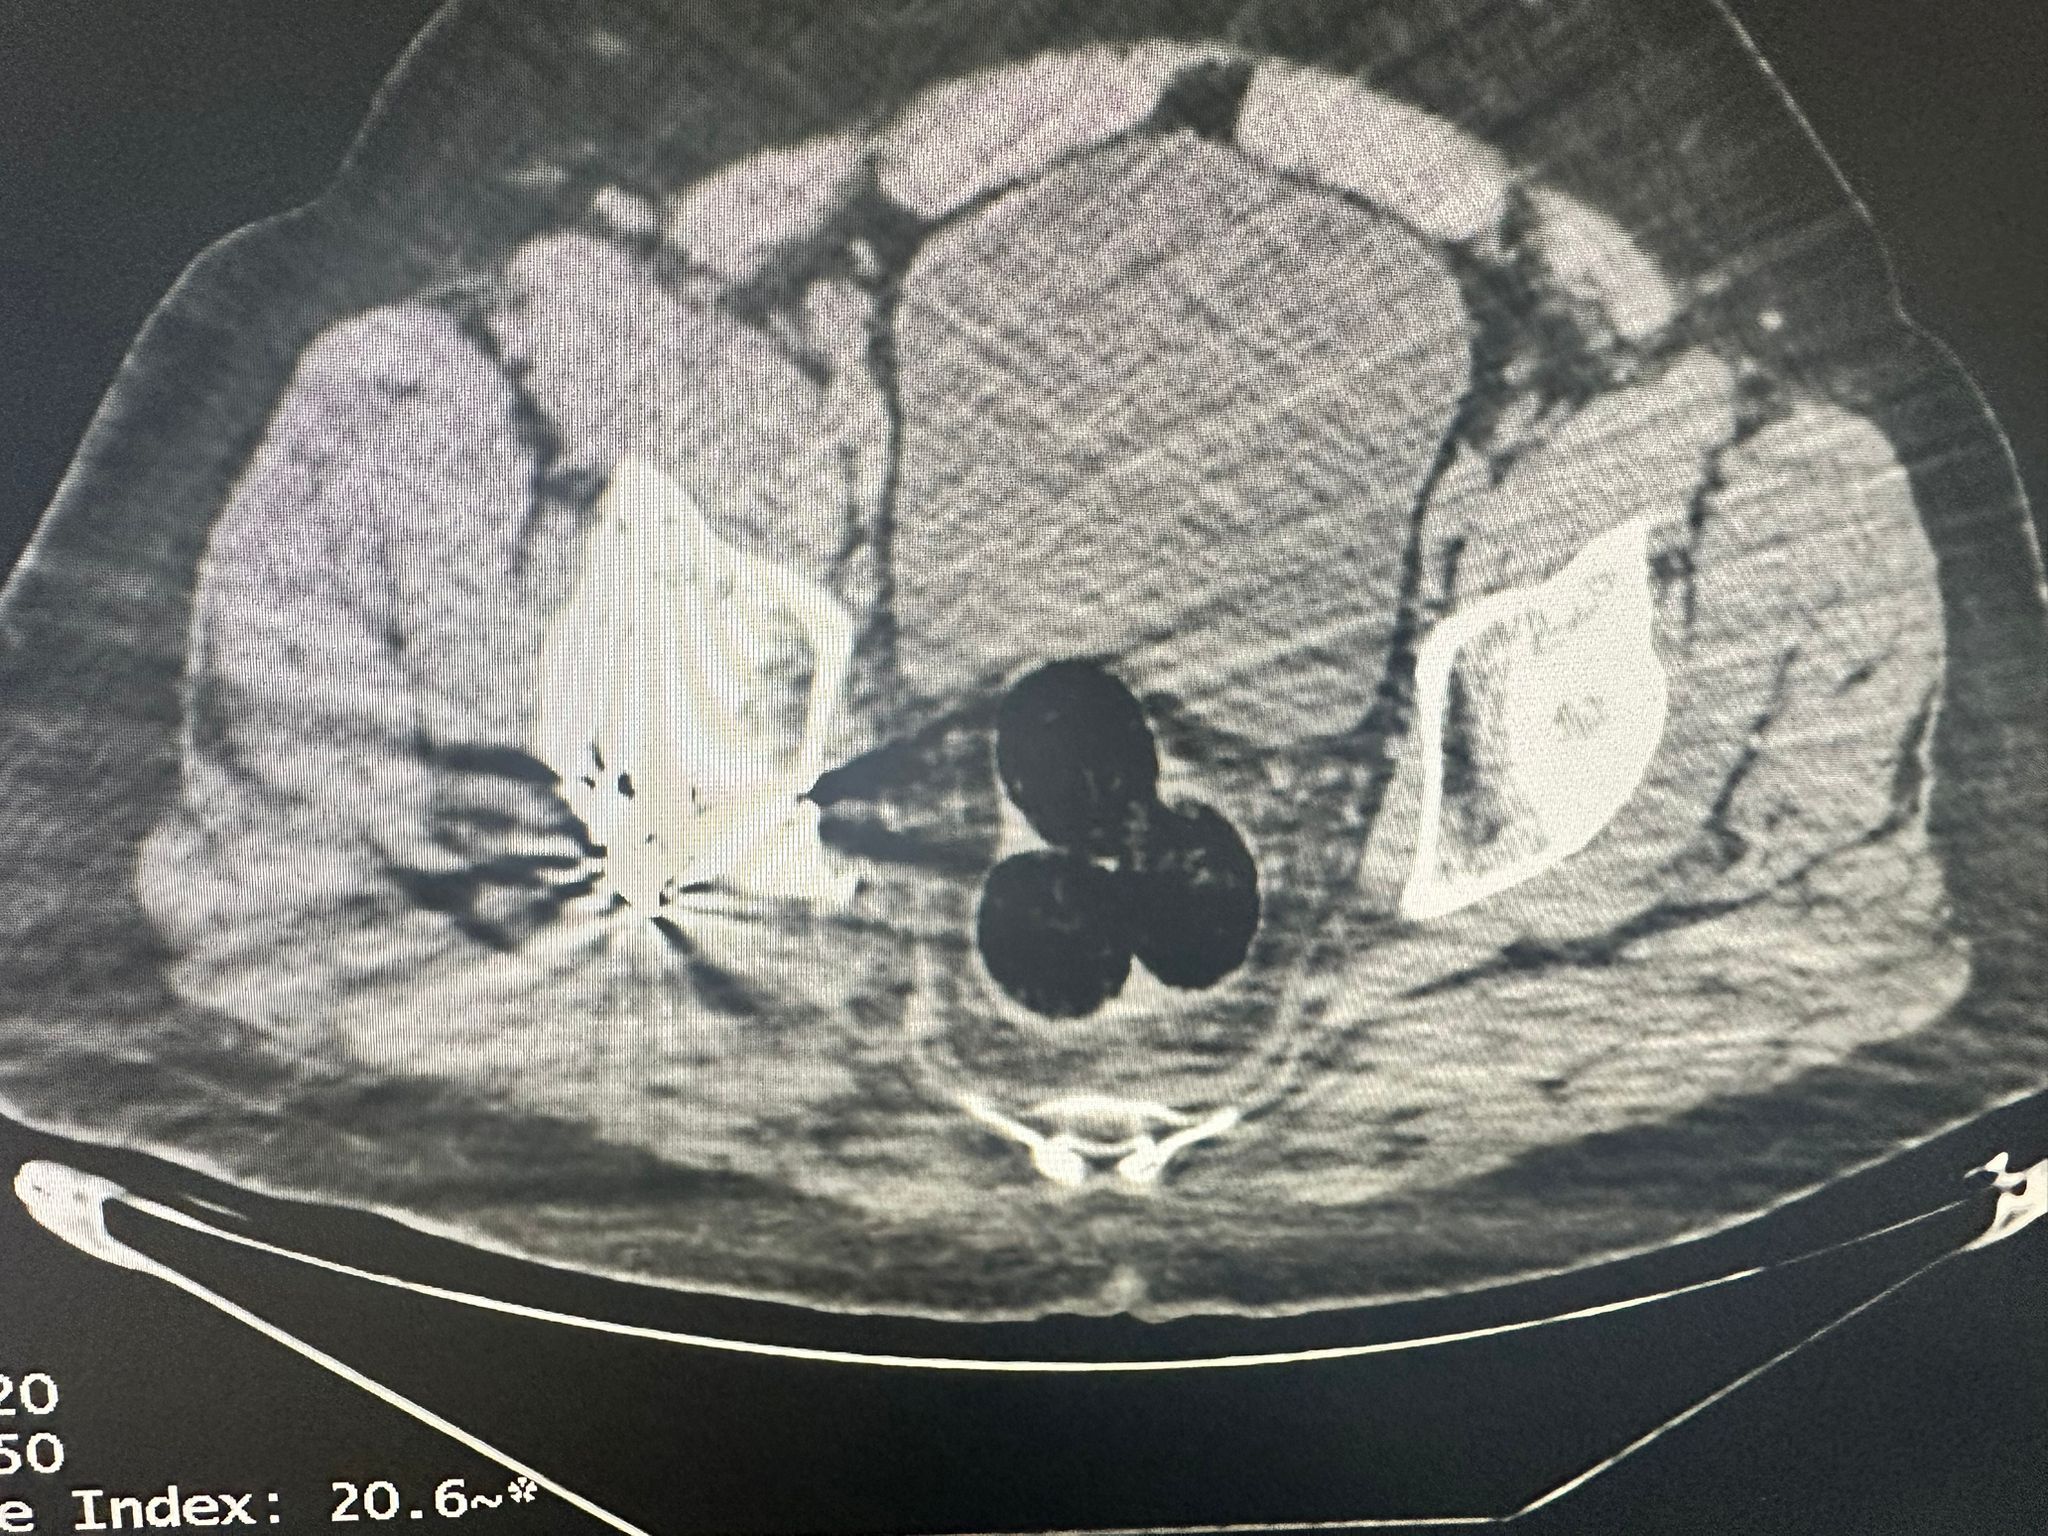

İran’dan ülkeye giriş yapan ve uyuşturucu maddeleri vücut boşluklarında taşıdığı değerlendirilen yabancı uyruklu bir şahıs takibe alındı ve il merkezinde yakalandı. Şahsın radyolojik görüntüleme yöntemiyle yapılan iç beden muayenesinde, vücudunda 3 parça halinde yabancı cisim olduğu tespit edildi. Bu cisimler çıkarılarak el konuldu.